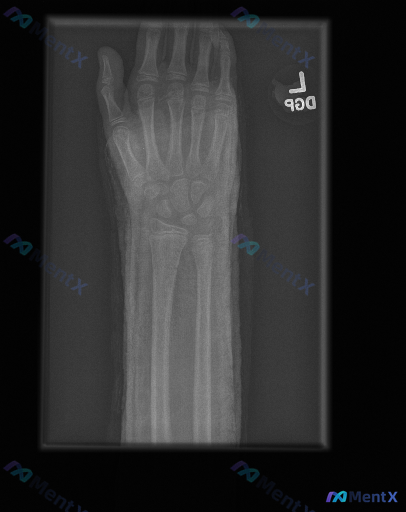

未成年人左手腕X光片,如何区分正常骨骺与可能的异常?

整理到一份未成年人左手腕及前臂正位X光片的影像资料,想跟大家讨论一下阅片判断的逻辑。

- 受试者:未成年人(影像提示骨骺尚未闭合)

- 检查部位:左手腕及前臂(正位)

- 骨骼发育:可见明显骨骺板(生长板),骨化中心发育与年龄相符

- 骨折筛查:桡骨/尺骨远端皮质连续性尚好,未见明确骨折线、中断或台阶征;腕骨形态、排列正常;近排掌骨基底部完整

- 关节对位:桡腕关节、下尺桡关节位置正常;腕骨Gilula弧线基本连续

- 软组织与骨质:周围软组织无明显肿胀;骨小梁清晰,无骨质破坏、骨赘或明显疏松;无异常高密度异物

目前的核心讨论点是:这张影像里的“线性透亮影”该如何解读?结合整体情况,大家第一反应会更倾向于哪种判断?